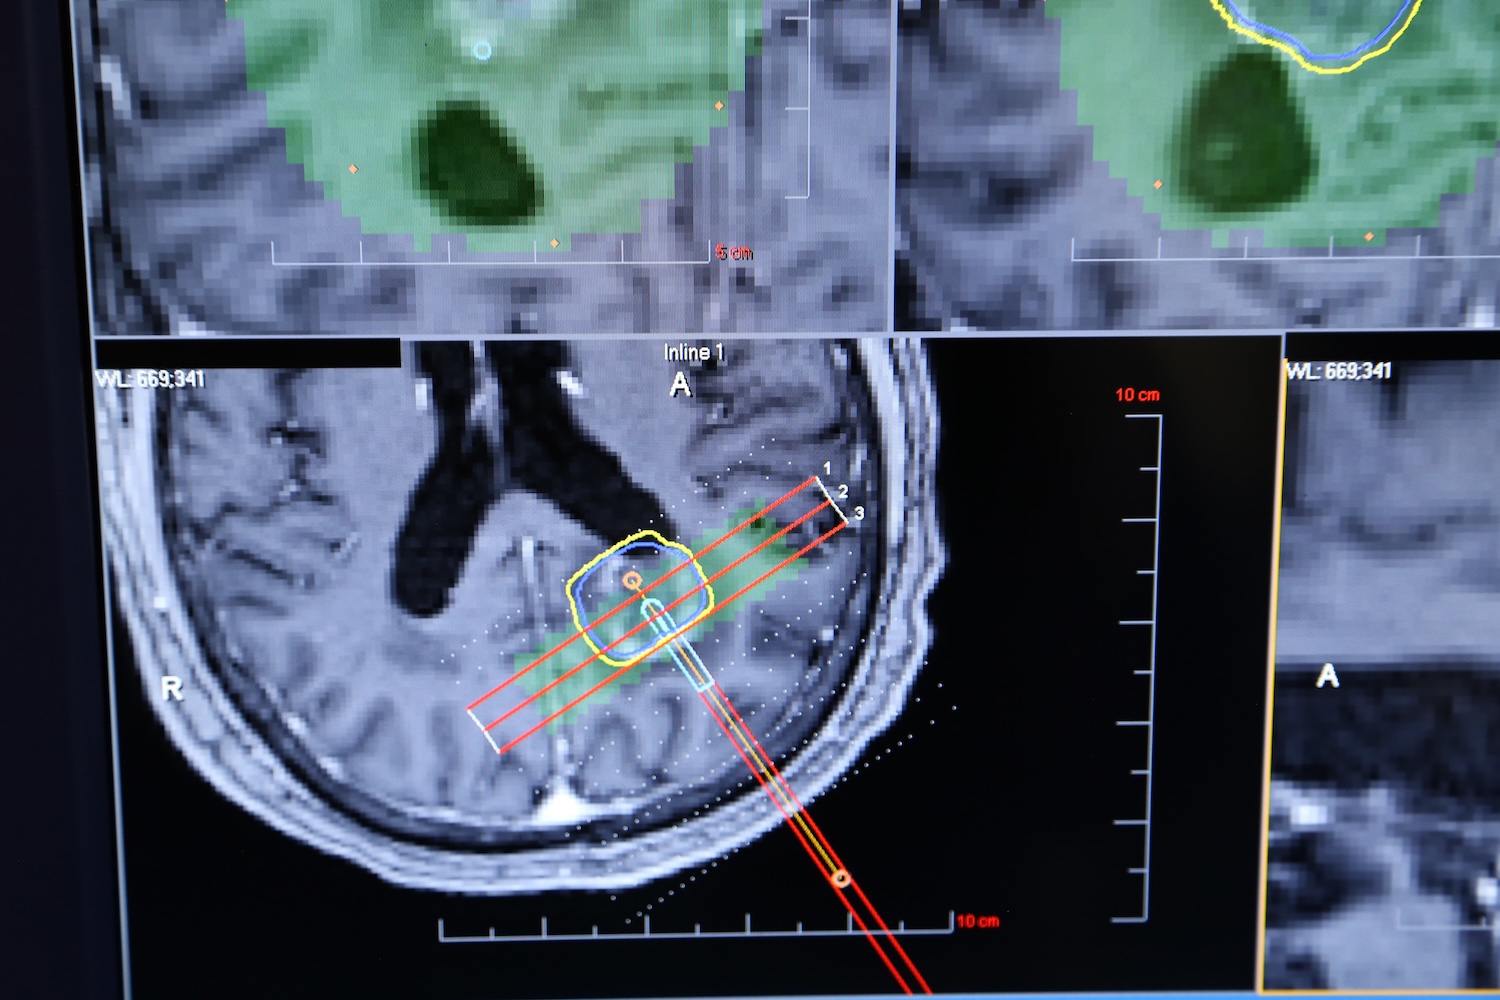

LITT, sometimes called “laser ablation,” is a technique that uses controlled heat to destroy abnormal brain tissue. The procedure is performed using the ROSA robotic system, which allows for sub-millimeter accuracy when placing a catheter with a precise trajectory and depth needed to safely reach the tumor.

Once the trajectory is set, the ROSA robot guides placement of the LITT catheter, which has a specialized tip that heats up to thermally damage the tumor and surrounding targeted tissue.

After bolt placement in the operating room, the patient is taken to an MRI suite, where another robotic system ensures the device is positioned exactly where it needs to be within the brain.

“During the ablation, surgeons monitor the temperature in real time through MRI imaging, allowing them to see exactly how the heat is affecting the tumor,” Gersey explains. “If critical structures are nearby, the system can limit or block heat from spreading into those areas. Should temperatures rise too high, the system will automatically shut down.”